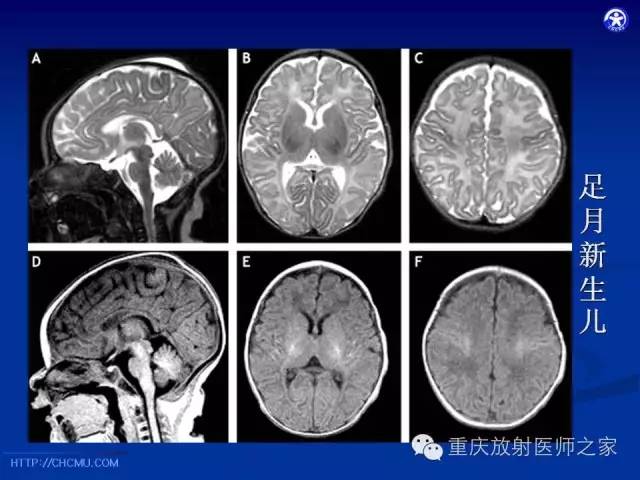

脑白质髓鞘化及相关疾病的MRI表现